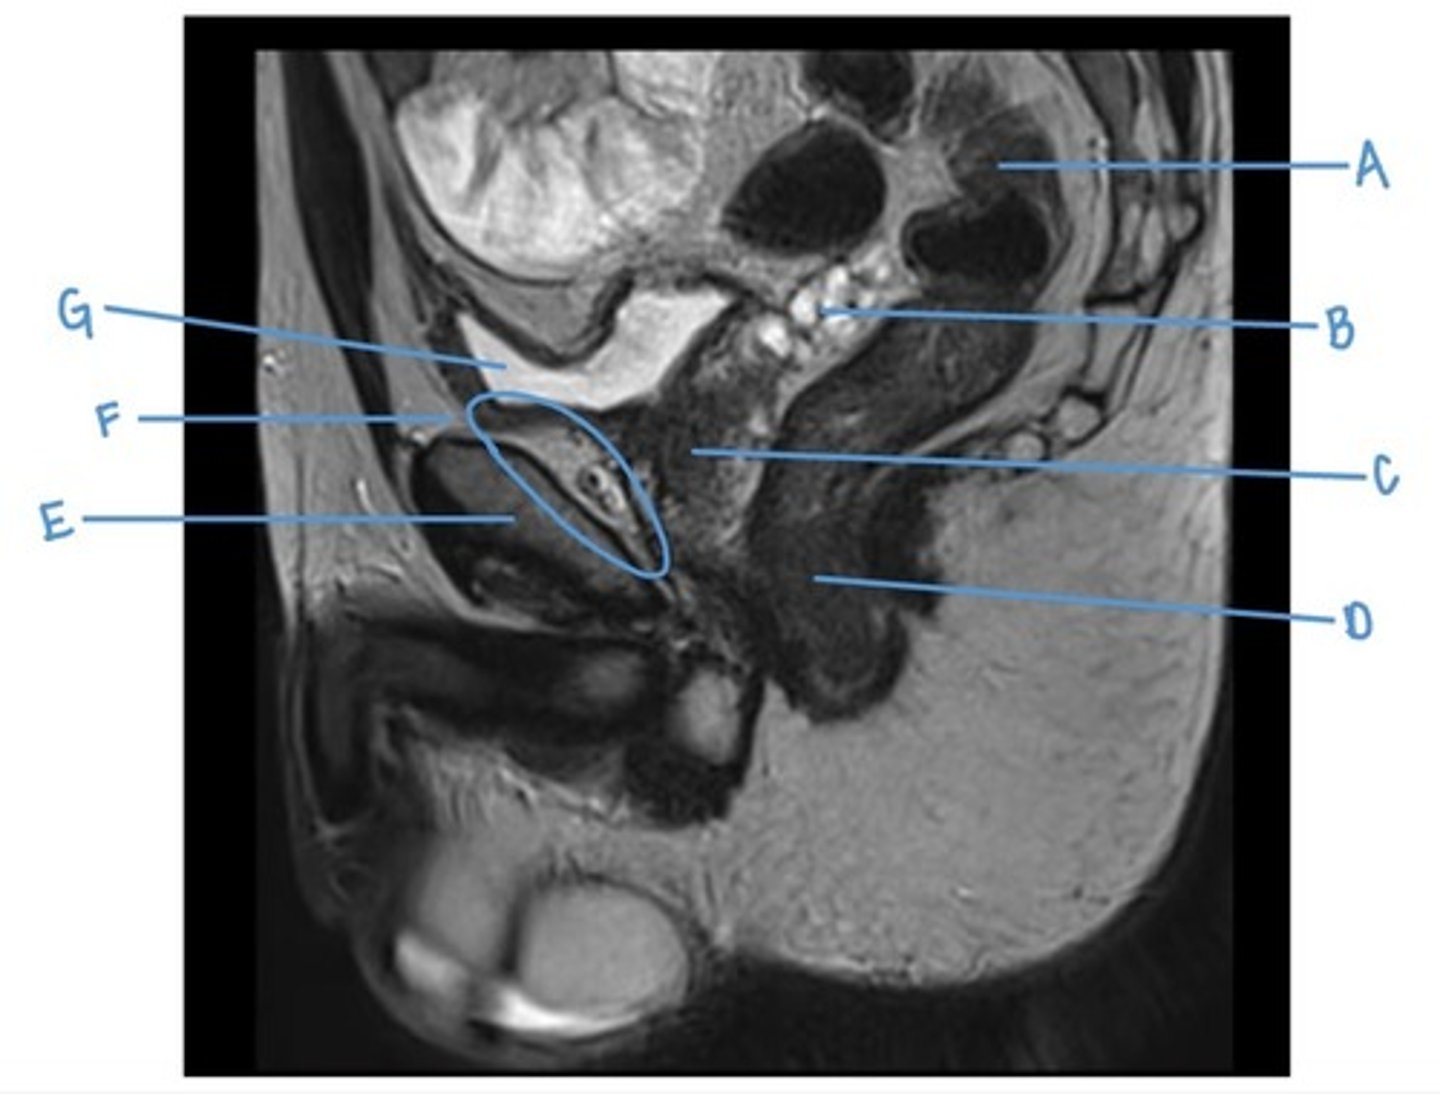

sacral promontory

A

sigmoid colon

B

vagina

C

rectum

D

urethra

E

pubic symphysis

F

retro-pubic space

G

bladder

H

uterus

I